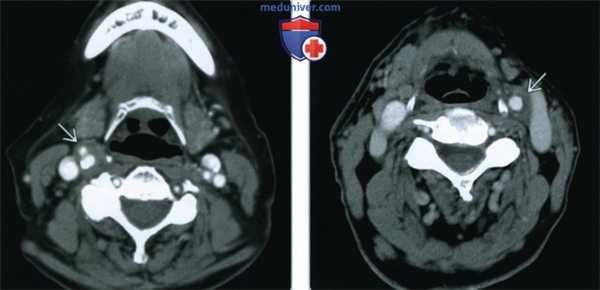

(Слева) КТ с КУ шеи, аксиальная проекция. Циркулярное утолщение стенки общей сонной артерии в области бифуркации. Был выставлен предположительный диагноз каротидинии, симптомы разрешились спустя 36 часов после назначения глюкокортикоидов.

(Справа) КТ с КУ в аксиальной проекции, картина, характерная для острой идиопатической каротидинии. Гомогенное мягкотканное образование, которое заключает в себя дистальный конец левой общей сонной артерии. Выраженного сужения просвета сосуда нет.

2. КТ при острой идиопатической каротидинии:

• Гомогенное утолщение стенки сонной артерии

• Контрастное вещество накапливает плохо или не накапливает вовсе

• Расслоение сонной артерии с ее тромбозом, либо бляшка низкой плотности могут выглядеть точно так же